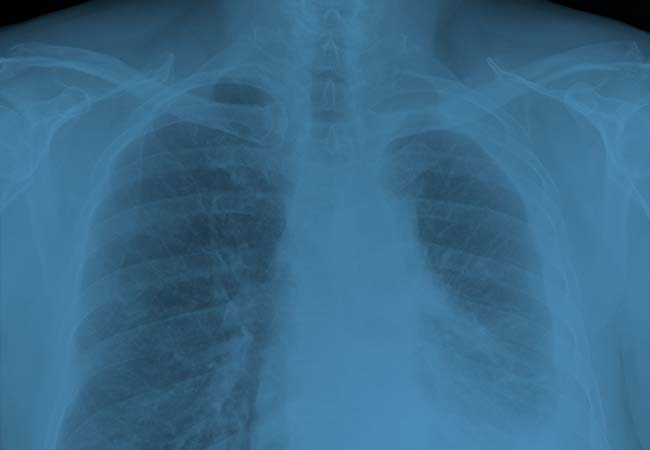

Asbestos-related illnesses, including mesothelioma, develop in the lungs or abdomen as a result of exposure to asbestos. Although symptoms may not develop for years, this exposure can cause serious, deadly diseases and cancers. If you or a loved one is suffering from illnesses caused by asbestos exposure, or have been diagnosed with mesothelioma, filing a…